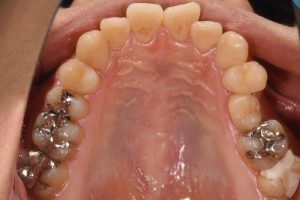

完成したセラミックインレー

治療後